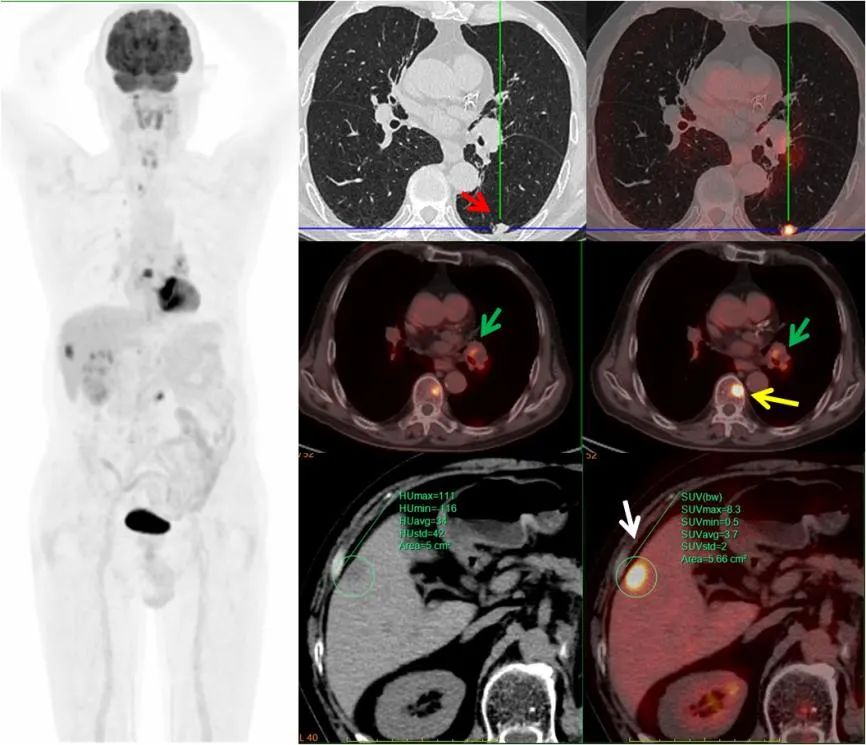

病例3,中年男性,左肾癌术后三个月,PET/CT示左肺下叶(红箭)、左肺门淋巴结(绿箭)、肝脏(白箭)、多发椎体(黄箭)高代谢灶,考虑左肺下叶原发MT可能,病理证实为小细胞神经内分泌癌。